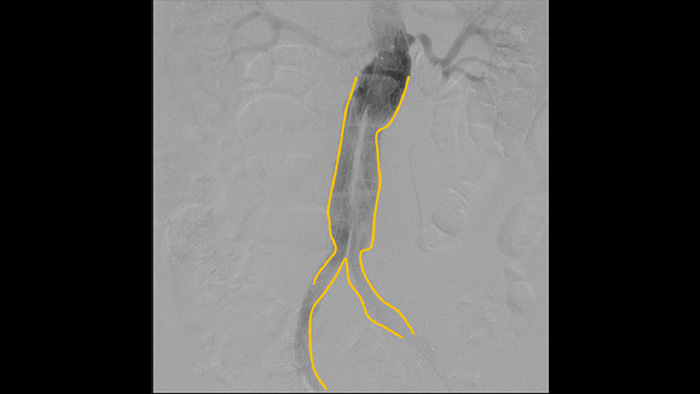

Digital subtraction angiography (DSA) is used in interventional vascular procedures to clearly visualise blood vessels by removing structures that can obscure vessel visibility. Roadmap fluoroscopy overlays a previously acquired subtracted contrast image on the live fluoroscopy, allowing you to track a device without reinjecting contrast.

Use the Outlining tool to easily mark a bifurcation or side branches by simply drawing on the monitor of the Mobile Viewing Station with your finger or an externally connected mouse.